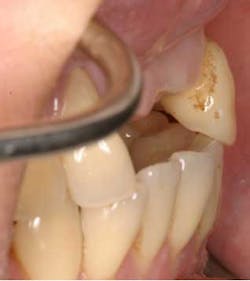

A 43-year-old female with a noncontributory medical history taking no medication and having no known food/drug allergies presented to my general dental office with a chief complaint of having “loose teeth with an underbite.” Clinically, she had generalized, moderate, chronic periodontal disease and was missing teeth Nos. 8 through 10. She had a Class III malocclusion with pathologic flaring of her remaining anterior teeth. She had both vertical and horizontal tissue loss in the No. 8 through 10 region. The patient wore a transitional partial denture to replace the anterior missing teeth that was placed in edge-to-edge occlusion by her previous dentist. (Fig. 1) She did not like having a removable prosthetic and desired a fixed option in the form of implants to replace her missing teeth. I sent her to the periodontist for a periodontal consult for her remaining dentition and dental implants to replace her missing front teeth.